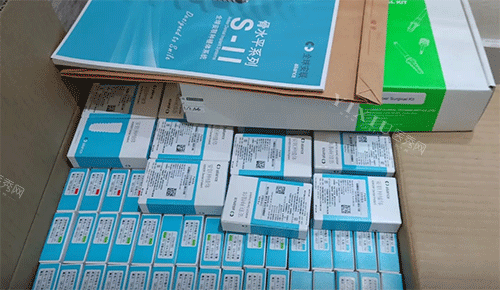

后来,我听朋友说有一家口腔医院不错,医生很正规,技术也可靠。我就抱着试试看的心态去了这家医院。到了医院,医生给我做了详细的检查,拍了片子,分析了我的口腔情况。医生说我的牙槽骨萎缩比较重的,但可以采用 “ALL - ON - N 桥式种植技术”,用 10 颗植体就能修养全口牙,而且手术时间短,修养也快。我听了之后,心里有点心动,但还是有点担心手术的风险和结果。